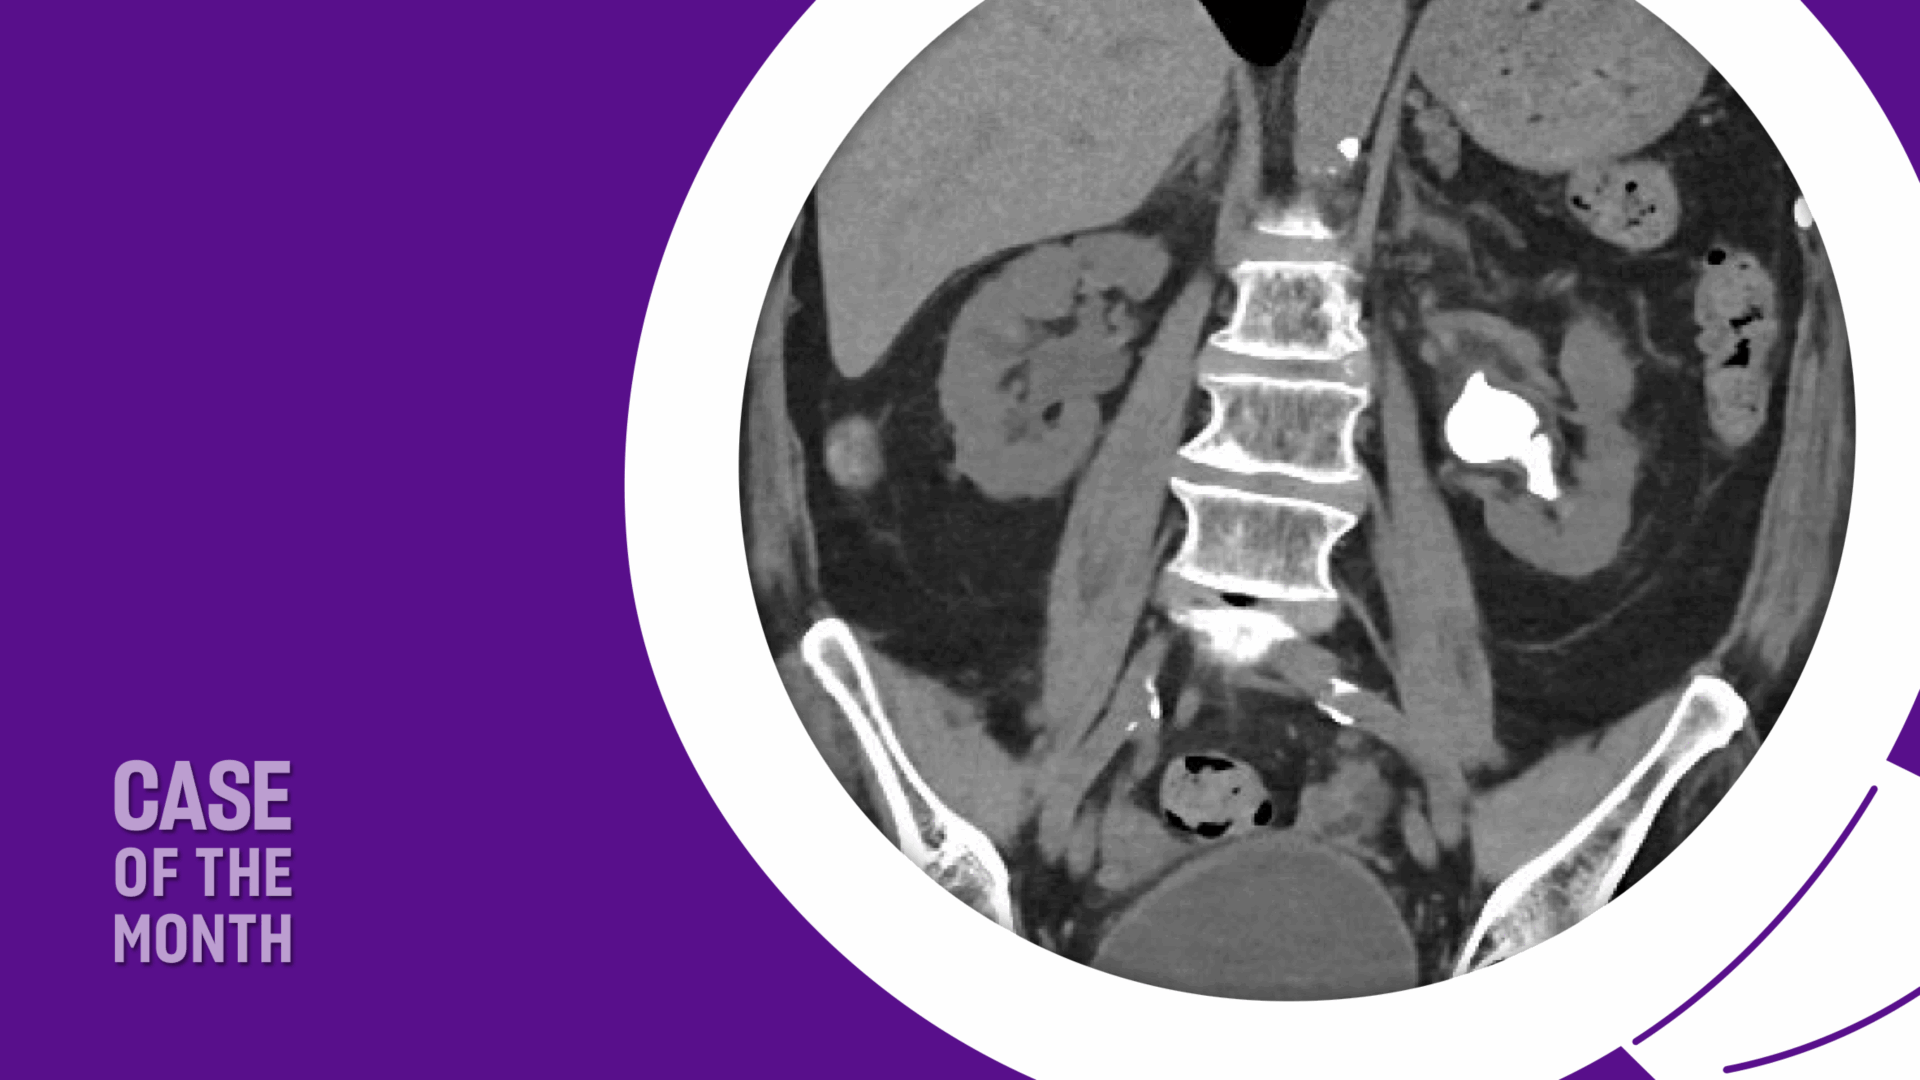

She presented with her children while completing a course of antibiotics and experiencing mild stent discomfort. She and her family preferred the least invasive option given her comorbidities, age, and religious beliefs, and sought to minimize bleeding risk as she declines transfusions. She required continued low-dose aspirin perioperatively but was able to temporarily hold apixaban for the procedure. After a detailed discussion of URS with laser lithotripsy, PCNL, and observation, the patient and family chose URS to address her recurrent infections and recent hospitalization. Preoperative imaging is shown in Figure 1.